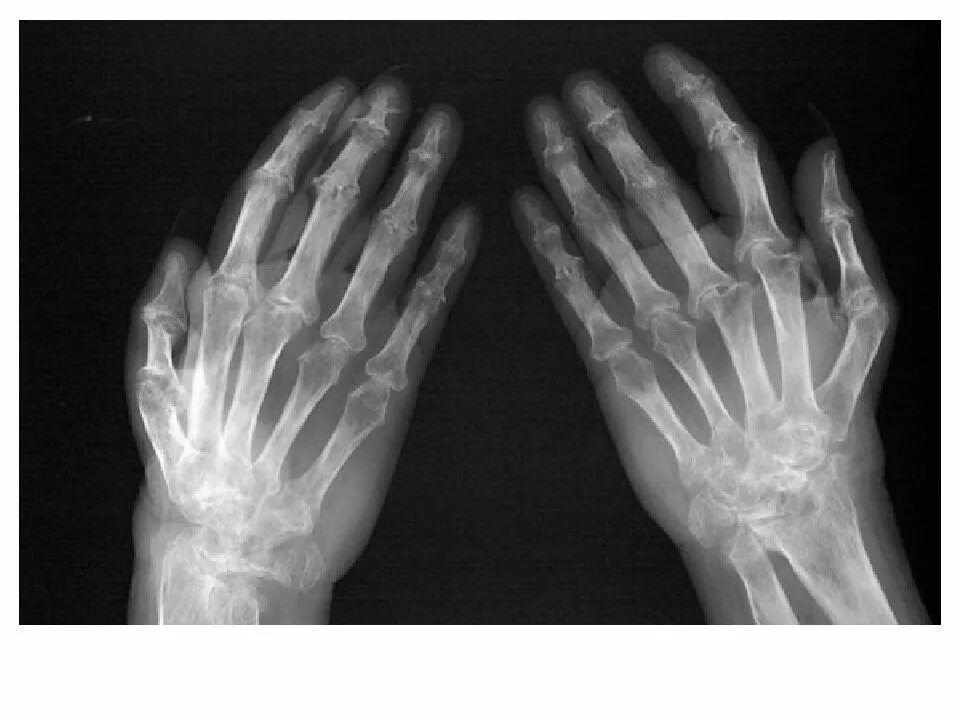

Артроз запястно пястного сустава